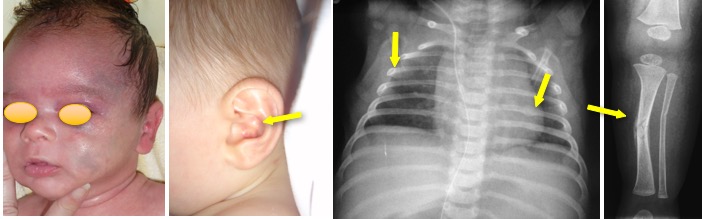

- des fractures multiples, souvent d’âges différents, intéressant les membres, les côtes…

- des ecchymoses diffuses, parfois évocatrice de la cause du trauma (morsures, gifles)

- un traumatisme crânien avec hématome sous-dural, fracture